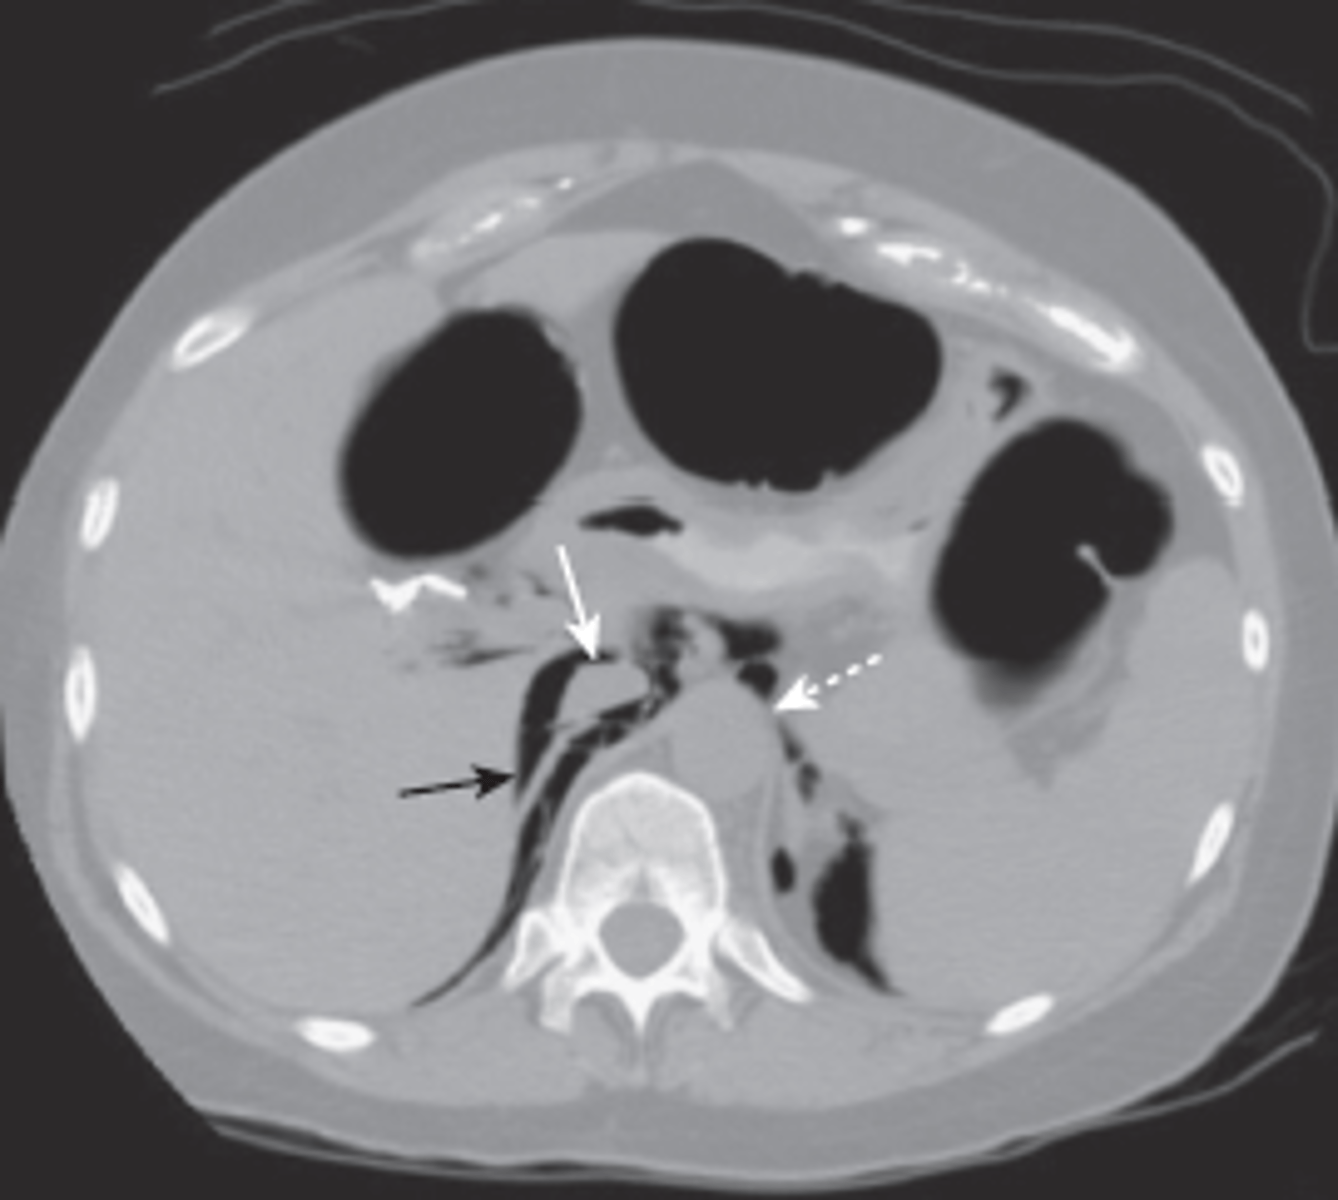

splenic laceration

hemorrhage and hematoma present, dark fluid is blood surrounding spleen